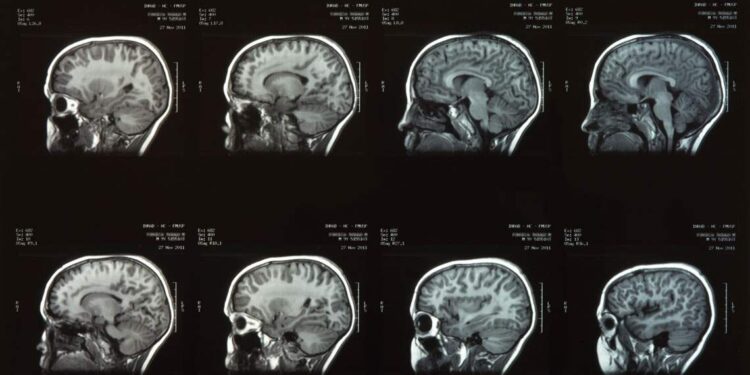

Pesquisadores da Universidade Duke, nos Estados Unidos, identificaram uma área no cérebro de ratos capaz de modificar a sensação de dor.

Liderado por Fan Wang, o estudo revelou que a amígdala, conhecida por seu envolvimento em emoções e ansiedade, também pode desempenhar um papel no alívio da dor. Essa descoberta pode influenciar futuros tratamentos para dor crônica em humanos.

A pesquisa concentrou-se em uma região específica da amígdala, onde neurônios, denominados de forma geral, foram ativados para inibir a dor. Quando estimulados, esses neurônios interromperam imediata e abruptamente os comportamentos indicativos de dor nos ratos.

Este achado oferece uma nova perspectiva sobre o controle da dor e apresenta esperança para terapias mais direcionadas.